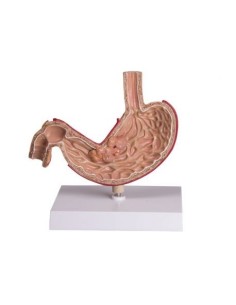

3B Modèle scientifique et anatomique : Pathologies de l'intestin K55